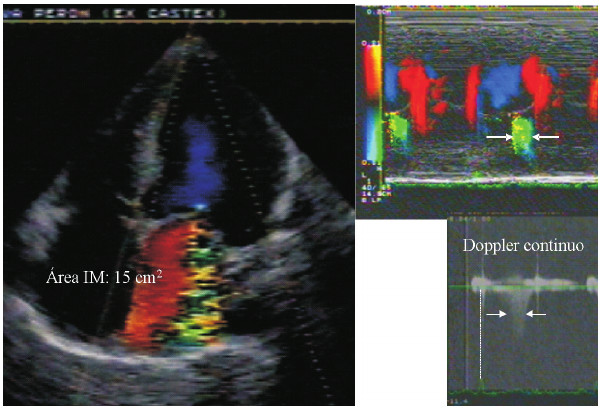

Una mujer de 45 años asintomática fue referida por presentar diagnóstico de insuficiencia mitral grave secundaria a prolapso de válvula mitral (Fig. 2). En el examen físico se auscultaba un soplo sistólico mesotelesistólico 3/6 creciente hacia el segundo ruido, irradiado hacia la axila, que aumentaba con la maniobra de hand grip, pero que no tenía tercer ruido. El eco-Doppler informaba un área del jet color de 12 cm2 y un orificio regurgitante efectivo de 36 mm2, compatibles con insuficiencia mitral grave, con la paciente normotensa. Sin embargo, el ventrículo izquierdo tenía diámetros normales, la aurícula izquierda estaba levemente dilatada y la velocidad pico de la onda E también era normal. En un nuevo estudio se pudo determinar que la insuficiencia mitral era solo telesistólica, momento en el cual se registró el área del jet y se calculó el orificio regurgitante por el método de PISA, asumiendo que la regurgitación ocurría durante toda la duración de la sístole y no solo en un tercio de ella. La ausencia de incremento de la velocidad pico de la onda E indica que el lleno rápido durante la diástole temprana es normal, y por lo tanto, el volumen regurgitante pequeño, lo cual se correlaciona con la ausencia de tercer ruido en la auscultación y el grado de insuficiencia mitral, que era leve.

Izquierda: vista de 4 cámaras apical evidenciando jet de insuficiencia mitral (IM). Derecha: modo M color y Doppler continuo, mostrando que la duración de la regurgitación ocurre durante el tercio final de la sístole.